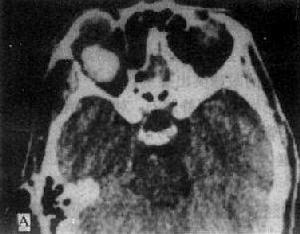

眼球破裂傷 CT掃描 診斷

眼球破裂傷CT掃描在眼眶內病變,眼內病變的眶外蔓延及顱內蔓延或眶周病變的眶侵犯等的診斷價值報導較多,而有關眼球破裂傷(鞏膜裂傷)的CT檢查的診斷價值報導較少,本文通過對眼球破裂傷(鞏膜裂傷)的CT徵象,原因和特點的討論,旨在提高診斷的準確率,指導臨床治療。

CT檢查能為眼球破裂傷提供重要依據,CT掃描密度解析度高,眼球環由鞏膜和眼外肌組成一個顯示中等密度(72Hu)之灰白色影像,密度稍低的玻璃體(21Hu)在環內顯示黑色影像,形成對比較明顯的圖像。同時CT還能進行冠狀位掃描及三維圖像重建,定位準備,可直接顯示眼環破裂口。其CT表現為:

(1)眼環不連續,並伴有局部不規則增厚,本組80.9%的傷眼可見到眼環某處呈線狀低密度影,提示眼環破裂所在部位。眼環正常厚度為2~4mm,本組病例中71.4%的眼環不同程度的局限性增厚。說明此徵象也是眼球破裂徵象之一。

(2)眼球變形,體積增大或縮小,與其對側眼相比,大於或小於4mm為增大或縮小,增大的原因是傷後被其他組織嵌頓閉合,合併球內出血等致眼球增大;縮小的原因為眼球破裂較嚴重,球內部分內容物脫出致眼球縮小。

(3)晶狀體缺如或脫位;由於較強的鈍力造成懸韌帶斷裂所致,尤其是晶狀體缺如,是眼球破裂的重要依據。

(4)其他徵象,如眼內出血,眼內積氣,眼球突出,眶骨骨折等都是眼球破裂傷的CT徵象。眶骨骨折可累及額竇、篩竇甚至合併腦挫傷,腦血腫,故檢查時應包括顱腦,細心觀察,注意調整窗寬,窗位。達到最佳顯示的程度。有學者認為前房加深是後鞏膜破裂的一個重要徵象。認為前房深度超過4mm或比正常眼側超過2mm即示後鞏膜破裂傷,但因缺乏準確的測量方法,本組未統計。眼球破裂傷幾乎所有的病例都有完全性前房出血 ,使得眼科常規的檢查無法進行,眼內損傷的情況不明,B超檢查只能發現球內出血和異物、網脫及晶體脫位等情況,但 對眼球壁、球後三角區及眼眶情況顯示不清,套用CT檢查,可彌補了這些不足,大大提高了診斷正確率。

因此,我們建議,在眼球鈍性挫傷後,臨床上有以下表現:(1)視力明顯下降;(2)球結膜下大量出血和水腫;(3)眼壓低;(4)前房大量出血,應懷疑有眼球破裂傷的可能,應即時行CT檢查。CT發現以下情況:(1)眼環不連續並伴有局部不規則增厚;(2)眼球變形或體積改變;(3)晶體缺如或脫位,提示有眼球破裂,結合CT定位情況,立即行眼球修補術,或根據傷情行其他聯合手術。